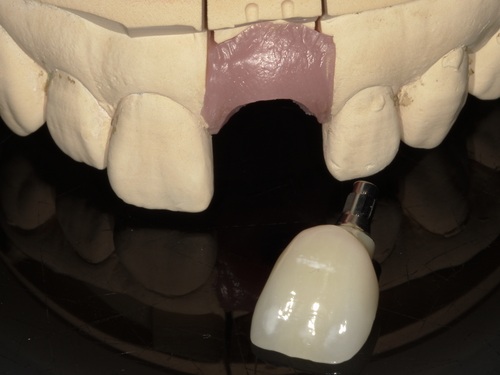

⑦セット

型取りから2週間ほどでジルコニアセラミックブリッジが完成してきました。

適合・色合い・噛み合わせに問題がないことを確認し、歯科用セメントでしっかりとセットしました。術前と比較して色も自然でとても美しい仕上がりかと思います。